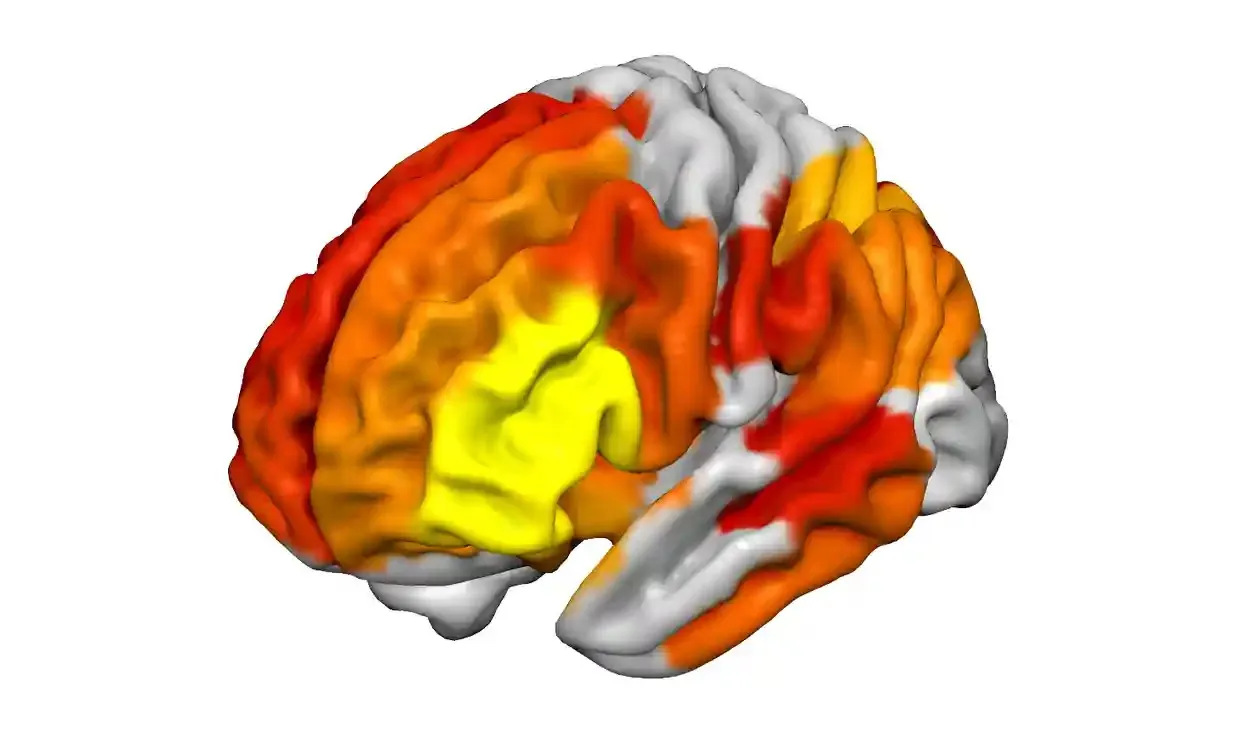

DMT Study gives most advanced picture yet of DMT compound’s effect on advanced functions such as imaginationFunctional magnetic resonance imaging (fMRI) scan of a brain shows regions of increased connectivity on DMT. Connectivity rises from yellow to orange to red. Photograph above: Christopher Timmermann, Imperial College London

For the latest study, Chris Timmermann, head of the DMT research group at Imperial College London, recruited 20 healthy volunteers who received a 20mg injection of DMT and a placebo on separate visits to the lab. All were screened to ensure they were physically and mentally suitable for the study.Using electroencephalography (EEG) and functional magnetic resonance imaging (fMRI), the scientists recorded the participants’ brain activity before, during and after the drug took hold. The volunteers gave updates throughout on how intense the experience felt. None vomited as the emetic is another ingredient in ayahuasca.The results, published in the journal Proceedings of the National Academy of Sciences, provide the most advanced picture yet of the human brain on psychedelics. The recordings show how the brain’s normal hierarchical organisation breaks down, electrical activity becomes anarchic, and connectivity between regions soars, particularly those handling “higher level” functions such as imagination, which evolved most recently in humans. “The stronger the intensity of the experience, the more hyperconnected were those brain areas,” said Timmermann.